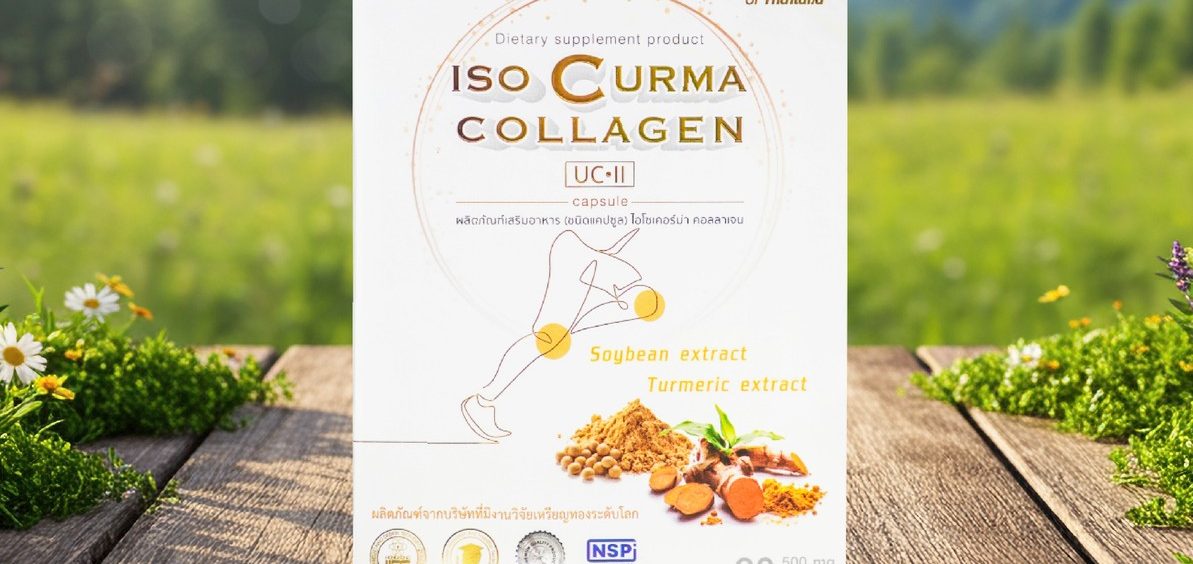

ISO CURMA COLLAGEN

C'est le traitement basé des plantes médicinales 100 % d'Asie, n'est pas dangereux pour le foin et les reins et sans les effets secondaires.

Ce remède naturel enregistré au près de la Ministère de l'alimentation et des médicaments en Thaïlande, n° enregistré :50-2-05159-5-0050.

Cette phytothérapie naturelle est certifieée et a reçu plusieurs Grands Prix Mondiaux.

Ce complément alimentaire est 100% naturel soigne l' Arthrose et les maladies Rhumatoïde :

Mode d'emploi :

Prendre ce remède naturel contre l'Arthrose :

1 comprimé par jour avec un verre d'eau et continuer à le prendre jusqu'à la fin de guérison.

Prix : 80 € l'unité, Livraison gratuite